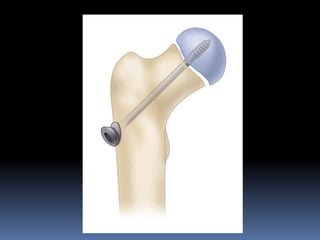

 INSITU PIN OR SCREW FIXATION –

Percutaneous in situ pinning most often used treatment in mild , moderate

& some severe acute or chronic slip.

Open insitu pinning – more severe acute or acute on chronic slip.

Use of single larger diameter central pin or screw is recommended –

technically simpler.

Use of pediatric cannulated screws over guide wire – easier & more

accurate.

Pins or screws shouldnot be removed until physis closes.

Generally two screws used for acute unstable slips & one for chronic stable

slips.

Pin tip be advanced to 8mm or one third of femoral head radius from

subchondral bone.

Pin or screw be placed in center of femoral head.

Advantage is it helps in minimizing skin incision.

Disadvantage is pin penetration, which can lead to joint sepsis, localized

acetabular erosion, synovitis, chondrolysis & late degenerativeOA.

Incidence of pin penetration – 14 to 60%